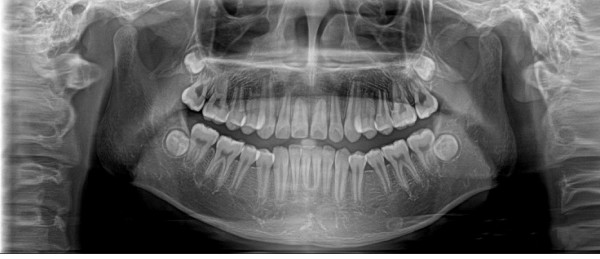

全景機基于體層攝影原理設計而成,全景攝影時,根據口腔頜面部的解剖特點,X線球管圍繞人體頭部選擇約120°,從一側顳下頜關節到另一側顳下頜關節,最后一次性獲得全口牙齒的2D圖像,使頜骨及全口牙體層攝影在一幅圖片上呈現左右展開的平面圖。

全景機具有觀察全面、操作簡便、兒童及老弱患者容易接受的優點。然而,全景機的缺點也非常明顯:

1.相較牙片機,全景成像中牙齒內部的清晰度和細節明顯要略遜一籌;

2.由于是曲線體層成像,其圖像有比較嚴重的畸變失真,同樣也不可避免的具有影像重疊。

因此,全景機主要用于觀察所有牙齒的形態、位置及頜骨內情況,為牙齒正畸矯正、牙齒修復提供圖像依據,不太適合用于對牙齒結構成像清晰度要求非常高的領域。